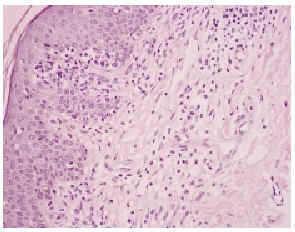

Una biopsia de la piel eritrodérmica mostraba un intenso infiltrado linfocitario pleomórfico, en banda subepidérmica, con epidermotropismo, así como fenómenos dispersos de exocitosis linfocitaria y microabscesos de Pautrier (figs. 2 y 3): el infiltrado linfocitario era positivo para CD4 y CD3, y negativo para CD22 y CD8 (fig. 4). El estudio histológico de una adenopatía mostró una infiltración específica por linfoma.

Fig. 2.--Infiltrado linfocitario subepidérmico, con epidermotropismo y fenómenos de exocitosis linfocitaria.